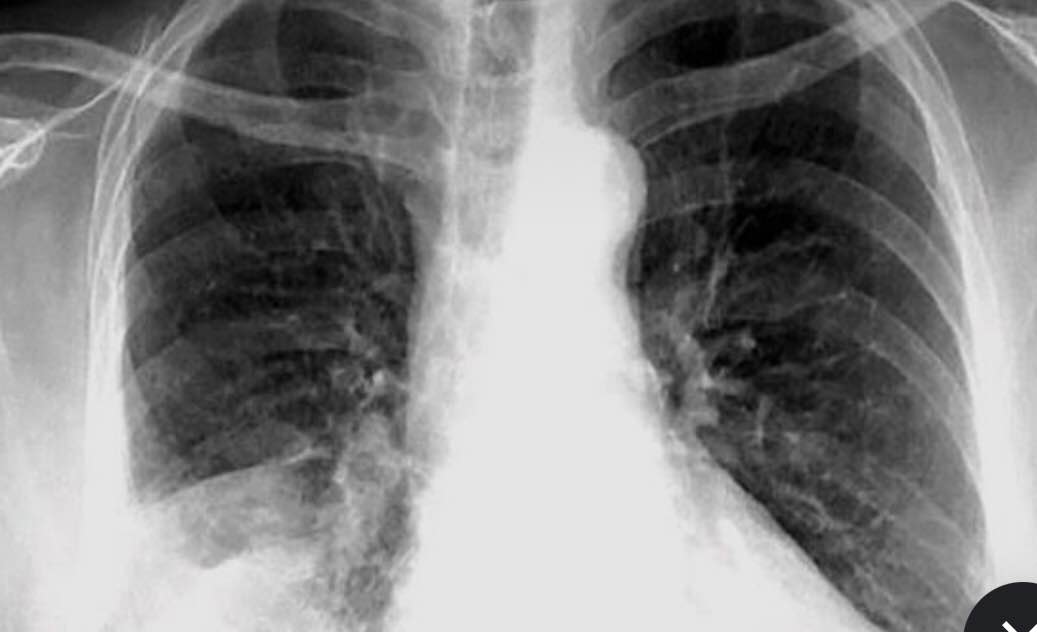

Pop Quiz Coughing With Sputum as a COPD Symptom Consultant360

From www.consultant360.com

From www.ccjm.org

Dyspnea and cough in a lung transplant recipient Cleveland Clinic Journal of Medicine Lung Pop When Coughing Rales (also called crackles) stridor. Pneumonia is an infection that inflames the air sacs in one or both lungs. Signs and symptoms of popcorn lung include: Learn more about the different sounds lungs can make and when someone should contact a doctor. Coughs may sometimes bring up mucus. These tubes carry air to and from your lungs. Breath sounds heard. Lung Pop When Coughing.